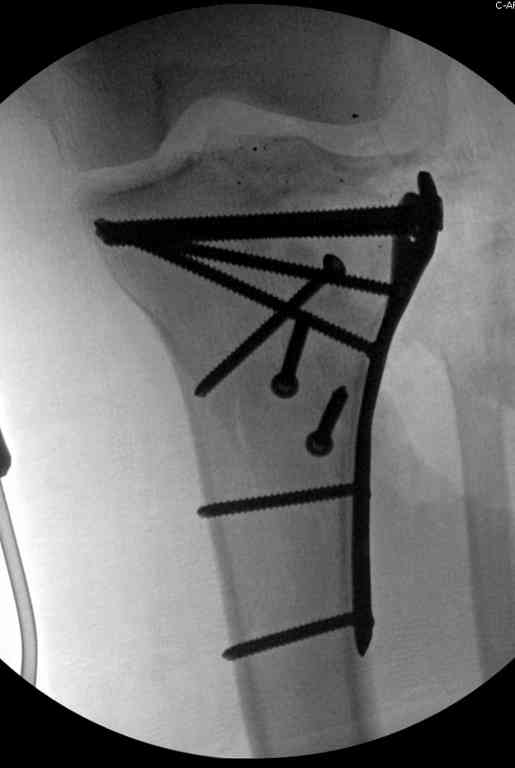

Имя     : 25 GSW flexur plate.jpg

Тип     : image/jpeg

Размер  : 28137 байтов

Описание: отсутствует

Url     : http://weborto.net:8080/pipermail/ortho/attachments/20100916/b1b36bf2/attachment-0011.jpg